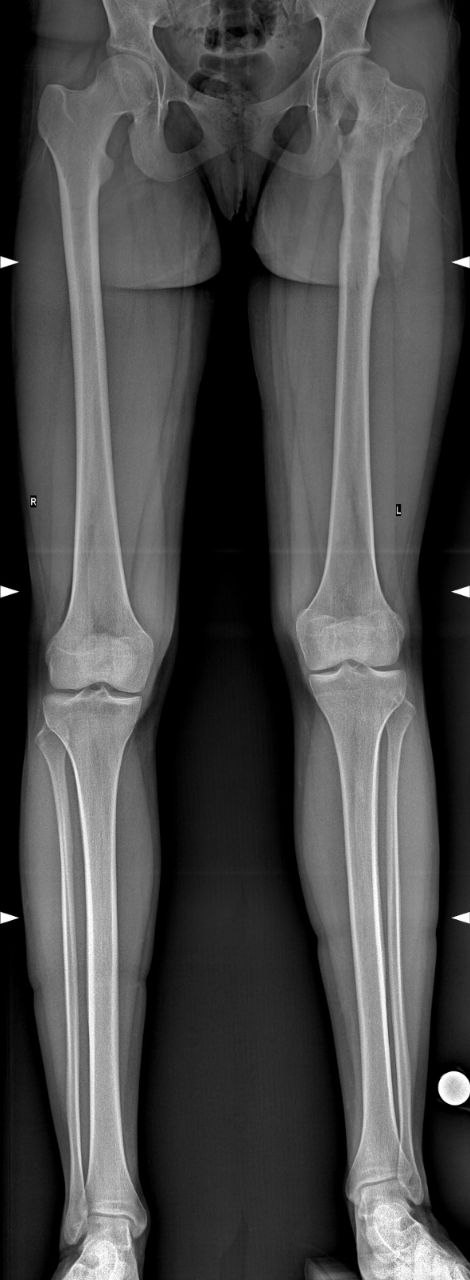

В случае подозрения на разновеликость, необходимо обратиться к детскому ортопеду для прохождения процедуры осмотра и выполнения дополнительных методов обследования. Из дополнительных методов обследования ведущее значение имеет панорамная рентгенография нижних конечностей (Full Leg).

Если разновеликость не критичная, в пределах до 1,0 см, возможно динамическое наблюдение с регистрацией темпов роста ребенка и рентгенологическим контролем. В случаях более значимой разновеликости, при условии функционирующих зон роста (до периода пубертата), методом выбора будет лечение по методу управляемого роста, заключающееся во временном блокировании зон роста бедренной или большеберцовой кости на здоровой конечности, с целью синхронизирования длины нижних конечностей.